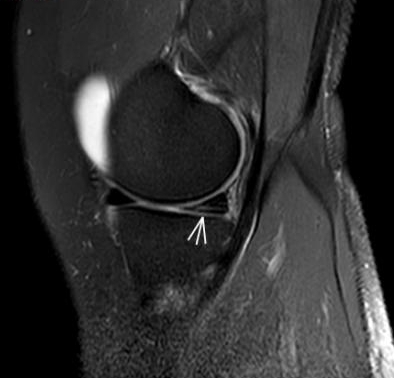

1. “咯吱響”+“卡頓感”——半月板的“碎玻璃警報(bào)”

場(chǎng)景:下蹲時(shí)膝蓋“咯噔”彈響,起身像被“卡住”

MRI偵查:精準(zhǔn)捕捉半月板撕裂或變性(半月板內(nèi)高信號(hào)),避免拖成“關(guān)節(jié)交鎖”

(半月板撕裂)